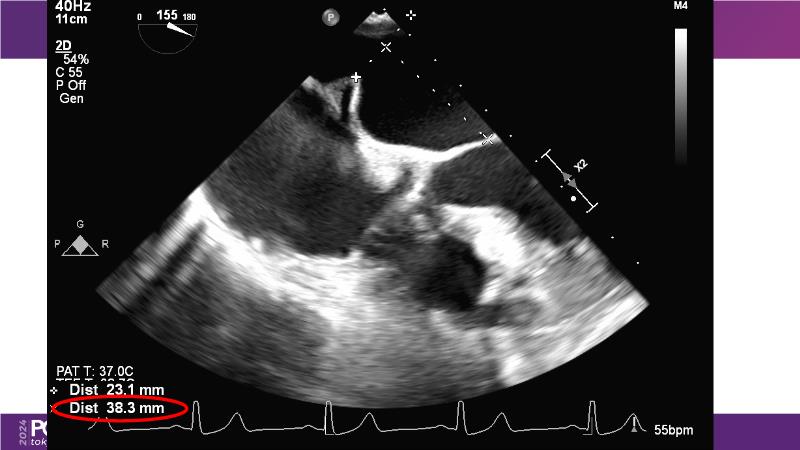

Watch this session to get an overview of a new TEER device, follow the step-by-step procedure related to initial experiences with this device for a Japanese patient with degenerative mitral regurgitation, learn about the latest data from RCT and registries, and follow discussions of challenging TEER cases!

- To learn procedural step-by-step of novel device